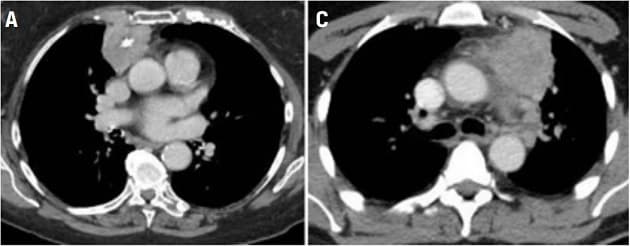

Eksempler på CT-billeder af tymom/thymuskarcinom med kontrast.